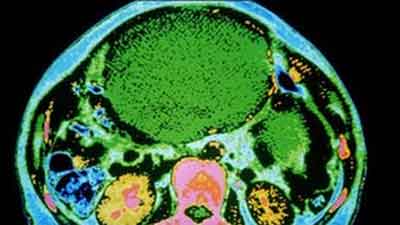

Pait Ma Charbi Cancer K Phelao Ka Sabab